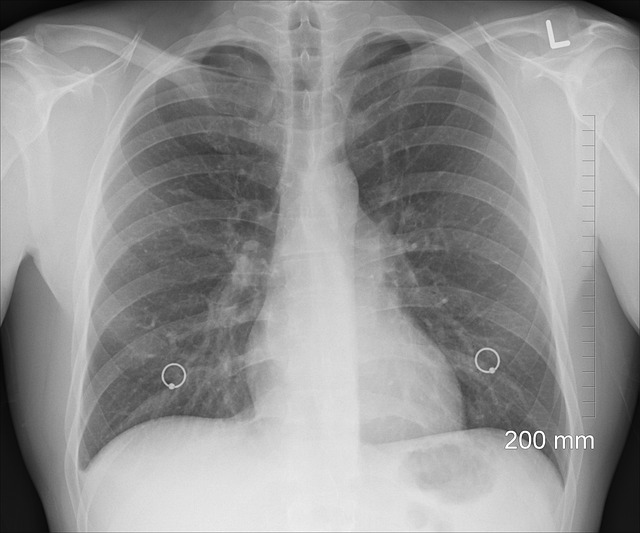

폐암은 조기에 발견되지 않으면 치명적일 수 있습니다. 따라서 폐암 초기증상을 알아야 합니다. 사람들은 호흡곤란, 지속적인 기침, 가슴 통증 등을 경험할 수 있습니다. 이러한 증상이 지속된다면 반드시 의사에게 상담해야 합니다. 폐암은 빠른 진단과 조기 치료로 예후가 크게 개선될 수 있는 질병입니다. 따라서 증상을 무시하지 말고 주변의 도움을 받아 조기에 대처해야 합니다.

폐암 초기증상은 폐암이 발생할 때 처음으로 나타나는 증상들을 말합니다. 이 증상들은 일반적으로 조기에 나타나지만, 많은 사람들이 이를 간과하고 무시하곤 합니다. 폐암 초기증상은 주로 기침, 가슴 통증, 호흡 곤란, 천명 소리, 피로, 체중 감소 등이 포함될 수 있습니다. 이러한 증상들은 다른 질병의 증상과 유사할 수 있으므로, 정확한 진단을 위해 의사와 상담하는 것이 중요합니다.

첫째로 (1) 기침과 가래가 지속적으로 나타납니다. 이는 기침이 두 달 이상 지속되거나 가래의 양이 많고 짙을 경우 더욱 주의해야 함을 의미합니다. 추가로, (2) 흉부 통증과 (3) 호흡곤란도 폐암 초기증상으로 나타날 수 있습니다. 통증은 가슴 속에서 느껴지며, 호흡곤란은 숨을 쉬기 힘들다는 느낌으로 나타날 수 있습니다. 마지막으로, (4) 체중감소와 피로감도 폐암 초기증상으로 주목해야 합니다. 체중이 갑자기 줄고, 지속적으로 피로하다면 폐암 가능성이 있습니다.